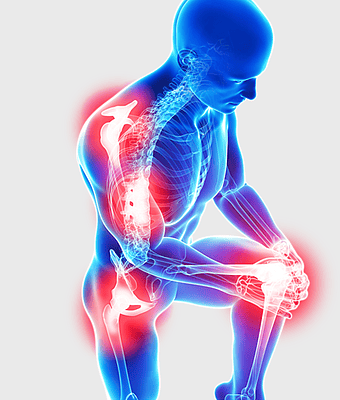

rheumatoid arthritis illustration, chronic pain therapy, joint replacement surgery, blue violet human skeleton, skeletal anatomy diagram, arthritis pain relief methods, orthopedic health visual aids -